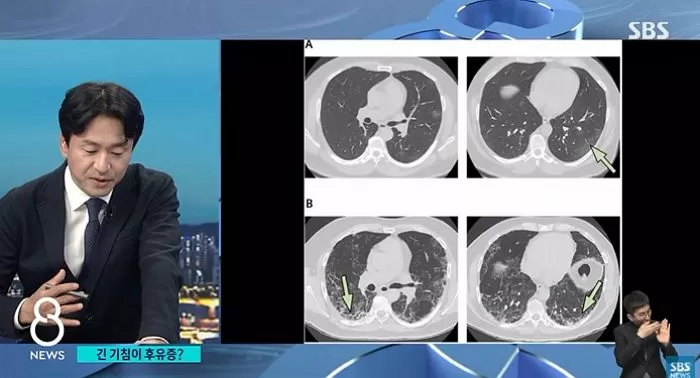

PCR에서 음성이 나왔는데도 계속 기침을 해서 허파 CT 찍었더니, 폐가 딱딱하게 굳는 섬유화가 진행됐고 뇌를 축소하는 증상도 확인된 것이다.

SBS에 따르면 중환자실에서 인공호흡기 치료까지 받았다면 대부분이 폐 섬유화가 진행됐다. 또 고령층·고혈압·당뇨병 등 기저질환자, 그리고 흡연자는 가볍게 앓더라도 폐가 굳을 위험성이 큰 것으로 나타났다.

폐 섬유화는 폐렴이 악화돼 발생하는 것으로 추정된다.

폐렴일 때는 회복될 수 있지만 폐가 굳은 다음에는 방법을 찾기 어려워 격리 해제 이후에도 기침, 호흡 곤란 지속되면 폐 CT 통해 빠르게 치료하는 것이 좋다.